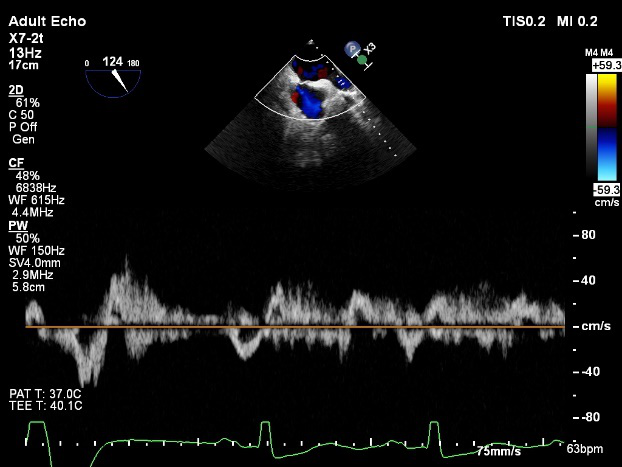

术前超声诊断:

长轴:左室下后壁节异,LAV:101ml,LVEDV:239ml

Bicom:MR(重度),返流束宽15.8mm,返流面积10.6cm²

PISA法定量EROA:0.69cm²,Rvol:168ml,RF:55%

肺静脉血流频谱呈收缩期反向

3D MV View

3D-color MV view:血流主要来源于2区近3区

Qlab软件勾画估测瓣口面积约:6.16cm²

二尖瓣口平均跨瓣压差:1mmHg

TEE Bicom返流量评估

TEE 4-Ch view返流量评估